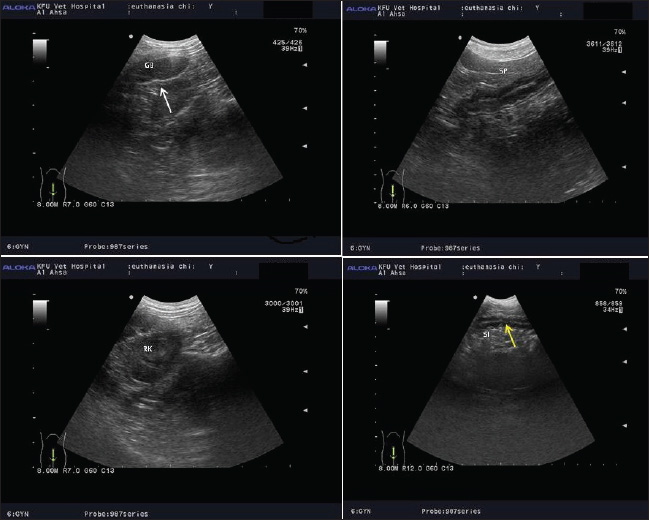

Notably, in one dog, a foreign body was detected in the gastrointestinal tract during the antemortem stage, which obscured the ultrasound imaging. During sedation, the dog expelled a large piece of gauze, and this foreign body was no longer visible in the postmortem imaging. This highlights a limitation of using ultrasound as a tool for PMI estimation, even though it can still be valuable for identifying surgical complications or failure of veterinarian treatment in dogs (Figs. 2 and 3). Necropsy of all dogs showed normal internal organs in all cadavers of dogs without regarding the previous veterinarian or surgical operation performed.

Fig. 2. Antemortem imaging of dogs under light anesthesia shows foreign body and masks the imaging for identification the boundary and demarcation of internal organs.

Fig. 3. The internal organs show reduction in echogenicity with unclear organ architecture at 2 and 4 hours after induction of euthanization at different times. Notably, the irregularity in the mucosa of gall bladder (whit arrow), irregularity of mucosa of small and large intestine (yellow arrow), changes in liver echogenicity, and unclear of vascularity in splenic paryenchyma were noticed at 2 and 4 hours after induction of death.

Notably, the irregularity in the mucosa of the gallbladder is a hallmark of early autolytic changes. The gallbladder is particularly prone to postmortem alterations due to its high content of digestive enzymes and bile, which can lead to enzymatic digestion of the mucosal lining. Histological studies have shown that mucosal desquamation and epithelial breakdown can occur within 1–4 hours after death, particularly in warm environments (Klimkowski et al., 2022).

Similarly, the irregularity of the mucosa in the small and large intestines (yellow arrow) reflects the early stages of autolysis. The gastrointestinal tract is one of the first organ systems to undergo decomposition because of its high bacterial load. The intestinal mucosa is rapidly disrupted as bacteria proliferate and tissue hypoxia progresses. Mucosal sloughing and submucosal edema can be observed as early as 2–4 hours postmortem (Pérez et al., 2020).

In addition, changes in liver echogenicity observed via ultrasonography indicate progressive hepatic cell lysis and the accumulation of intrahepatic gas or fluid due to autolysis and early putrefaction. Due to its large volume and rich blood supply, the liver undergoes predictable postmortem changes that can be detected within hours after death. The echogenicity may initially decrease due to fluid infiltration and increased cellular breakdown, but it later becomes heterogeneous due to gas formation (Wu et al., 2021).

Moreover, unclear vascularity in the splenic parenchyma may reflect early autolytic disruption of the splenic tissue architecture. The spleen typically softens and loses its definition as proteolytic enzymes break down cellular and connective tissues. Moreover, loss of vascular clarity can be associated with hemolysis and blood settling (livor mortis), which distorts normal imaging features (Roccarina et al., 2024).